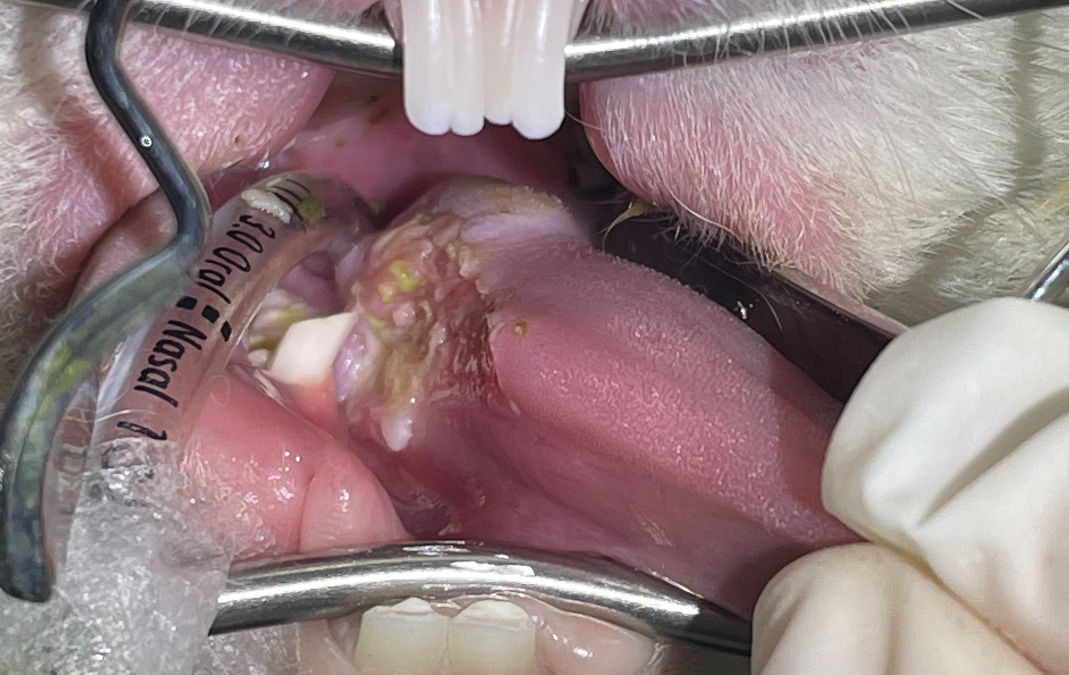

Dental procedures in rabbits and guinea pigs

British Veterinary Zoological Society, in collaboration with the Rabbit Welfare Association & Fund, recently released a position statement on the use of anaesthesia in rabbit and guinea pig dental procedures. This position statement states that conscious dental...